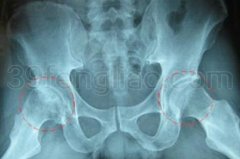

股骨头坏死辩证疗法

股骨头坏死辩证疗法 一、主要症状 股骨头坏死为常见的骨病之一。它的主要症状:第一,疼痛。疼痛可为间歇性或持续性,行走活动后加重,有时为休息痛。疼痛多为针刺样、钝痛或酸痛不适等,常向腹股沟区、大腿内侧、臀后侧和膝内侧放射,并有该区麻木感。第二,关节僵硬与活动受限。患髋…2015-09-06 15:18:41